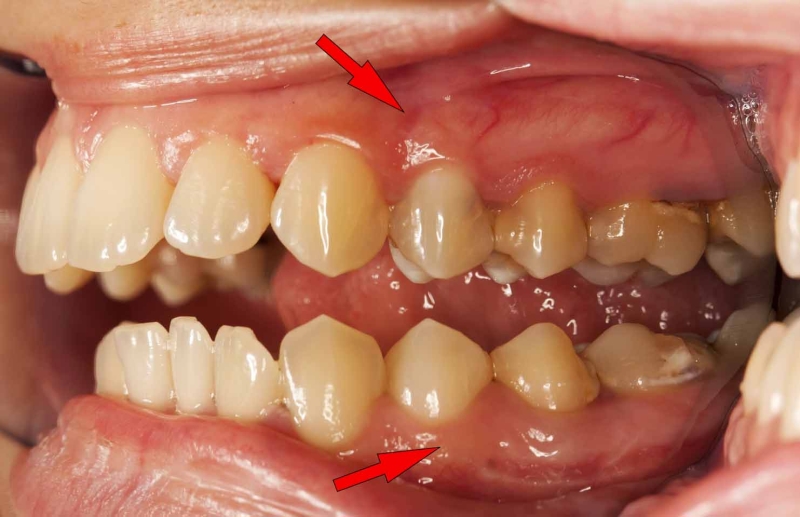

In the mouth, the healing phase presents as canker sores (aphthous ulcers) on the inside of the lips or cheeks, on the palate or tongue, or in all areas of the mouth, depending on the perception of the conflict situation (compare with aphthous ulcers related to the mouth surface mucosa). Canker sores appear as round or oval white spots with an inflamed border. They can be quite painful. On the gums, the pus-filled pocket is called a “dental abscess” or gum abscess. The tuberculous discharge causes bad breath.

HEALING PHASE: During the first part of the healing phase (PCL-A) the tissue loss is replenished through cell proliferation. Healing symptoms are swelling, water-filled blisters, redness (see “raspberry tongue” with scarlet fever), and possibly bleeding. On the lips, such blisters are commonly called “cold sores” or “herpes” (see also herpes related to the epidermis).

Gingivitis is restricted to the gum tissue. An inflammation of the gums might also arise during the healing of periodontosis. In this case, the condition is called periodontitis. In today’s dentistry, it is wrongly assumed that “gum diseases” are caused by dental plaque.